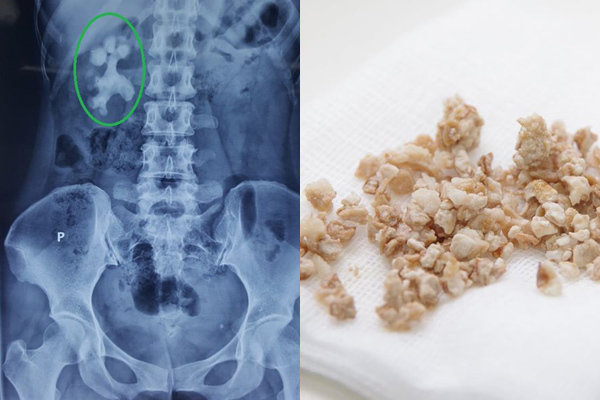

8. Ăn mặn gây sỏi thận

Sỏi thận là hậu quả của việc những chất dư thừa trong nước tiểu bị tích tụ lại và không đào thải được. Lâu dần, những chất này sẽ chuyển thành các tinh thể trong thận và ngăn trở đường di chuyển, đào thải của nước tiểu. Việc chúng ta ăn nhiều muối thường sẽ làm ta uống nhiều nước hơn, việc này cũng khiến thận của bạn phải hoạt động liên tục để đáp ứng nhu cầu thanh lọc của cơ thể, từ đó trở thành suy thận. Và khi thận hoạt động kém hiệu quả, theo thời gian sẽ xuất hiện các dấu hiệu của sỏi thận và nhiều căn bệnh liên quan khác.

Ăn mặn là nguyên nhân chính dẫn đến sỏi thận